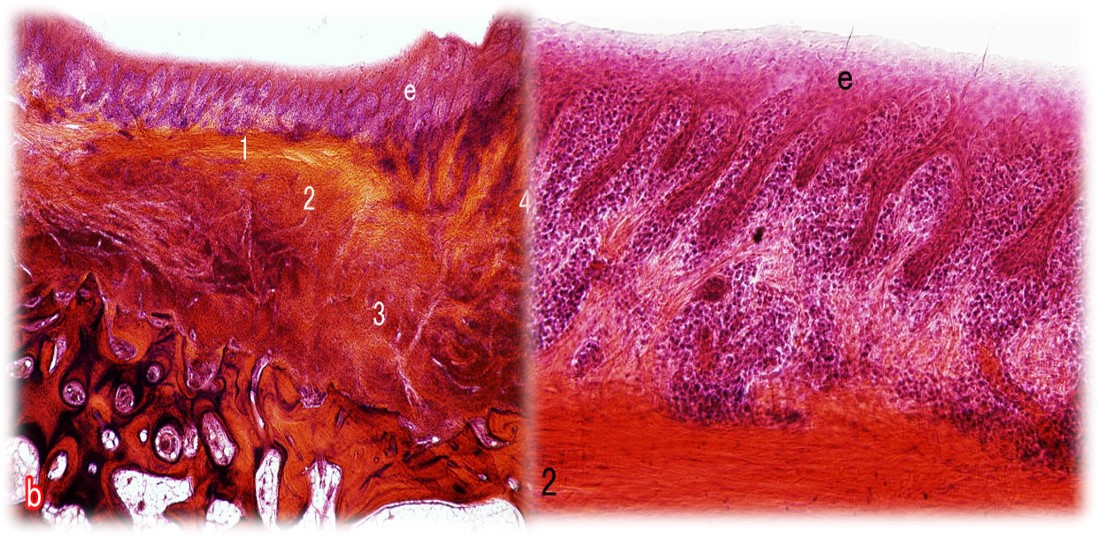

组织学特点:无角化,有钉突,炎症细胞浸润(图4.1-6);前磨牙区——楔形 磨牙区——低平;龈谷区易发生牙龈炎。

图4.1-6 龈谷上皮